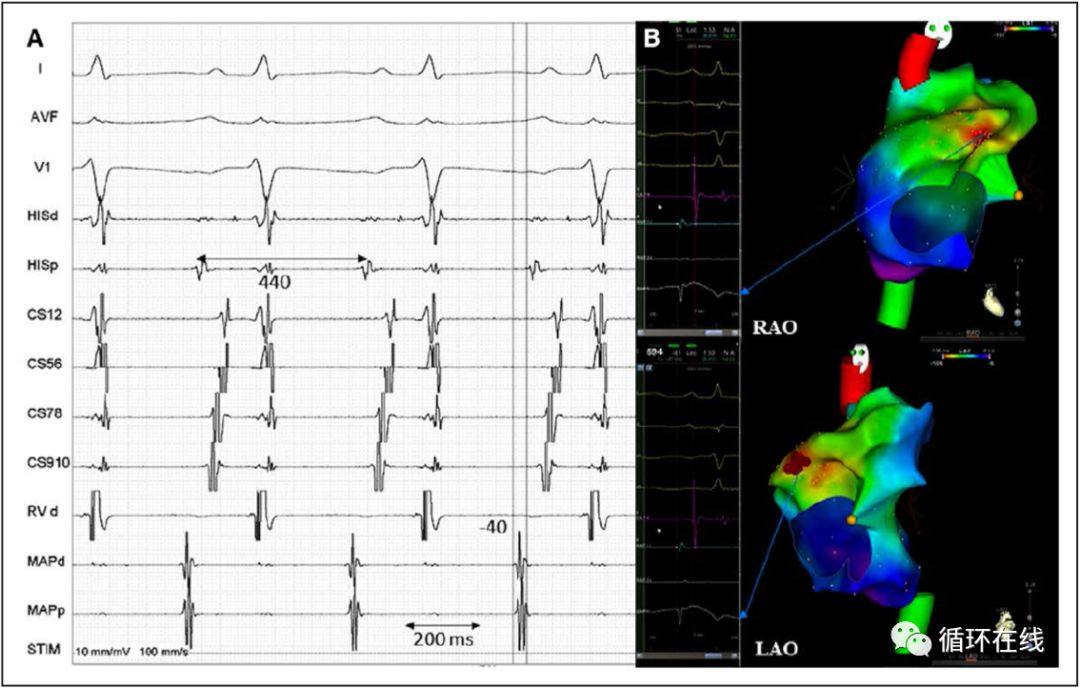

图3.1例无休止伊伐布雷定敏感房速的腔内电图和三维电激动图,提示最早激动点位于右心耳,提前体表P波40ms,局部进行射频消融终止房速。

临床心动过速时心房起搏 13 例患者中 11 例可超速抑制,未能终止或一过性拖带心动过速。其余 2 例患者中,FAT 自发终止并重新开始,发生温醒现象,提示自律性机制。伊伐布雷定有效组中有 10 例患者心动过速起源点位于右房,而3 例患者的FAT来源于左房。RA 起源房速中,起源部分如下右心耳 3 例,冠状窦口、界嵴上部和三尖瓣前外侧瓣环各 2 例,RA 游离壁 1例 。3 例左房房性心动过速均起源于左心耳。消融成功部位的局部电描记图在 P 波开始之前出现41.8±6.2 ms。所有患者均在激动标测指导下成功行射频消融,尽管输注异丙肾上腺素,等待 45 min 后仍不能诱发心动过速。心耳(右或左)心动过速的起源是伊伐布雷定有效的唯一预测因素(伊伐布雷定有效者 6/13,伊伐布雷定无效者 0/8,P= 0.046)。术后 1 例患者发生急性股动脉血栓栓塞,需要手术取栓。未观察到其他并发症。伊伐布雷定应答者中的患者在导管消融后无FAT复发。然而,伊伐布雷定无应答组中 1 例FAT来自右上肺静脉的患者在术后第二天复发临床心动过速,使用胺碘酮成功治疗。表 3 总结了伊伐布雷定应答者的临床和电生理特征。